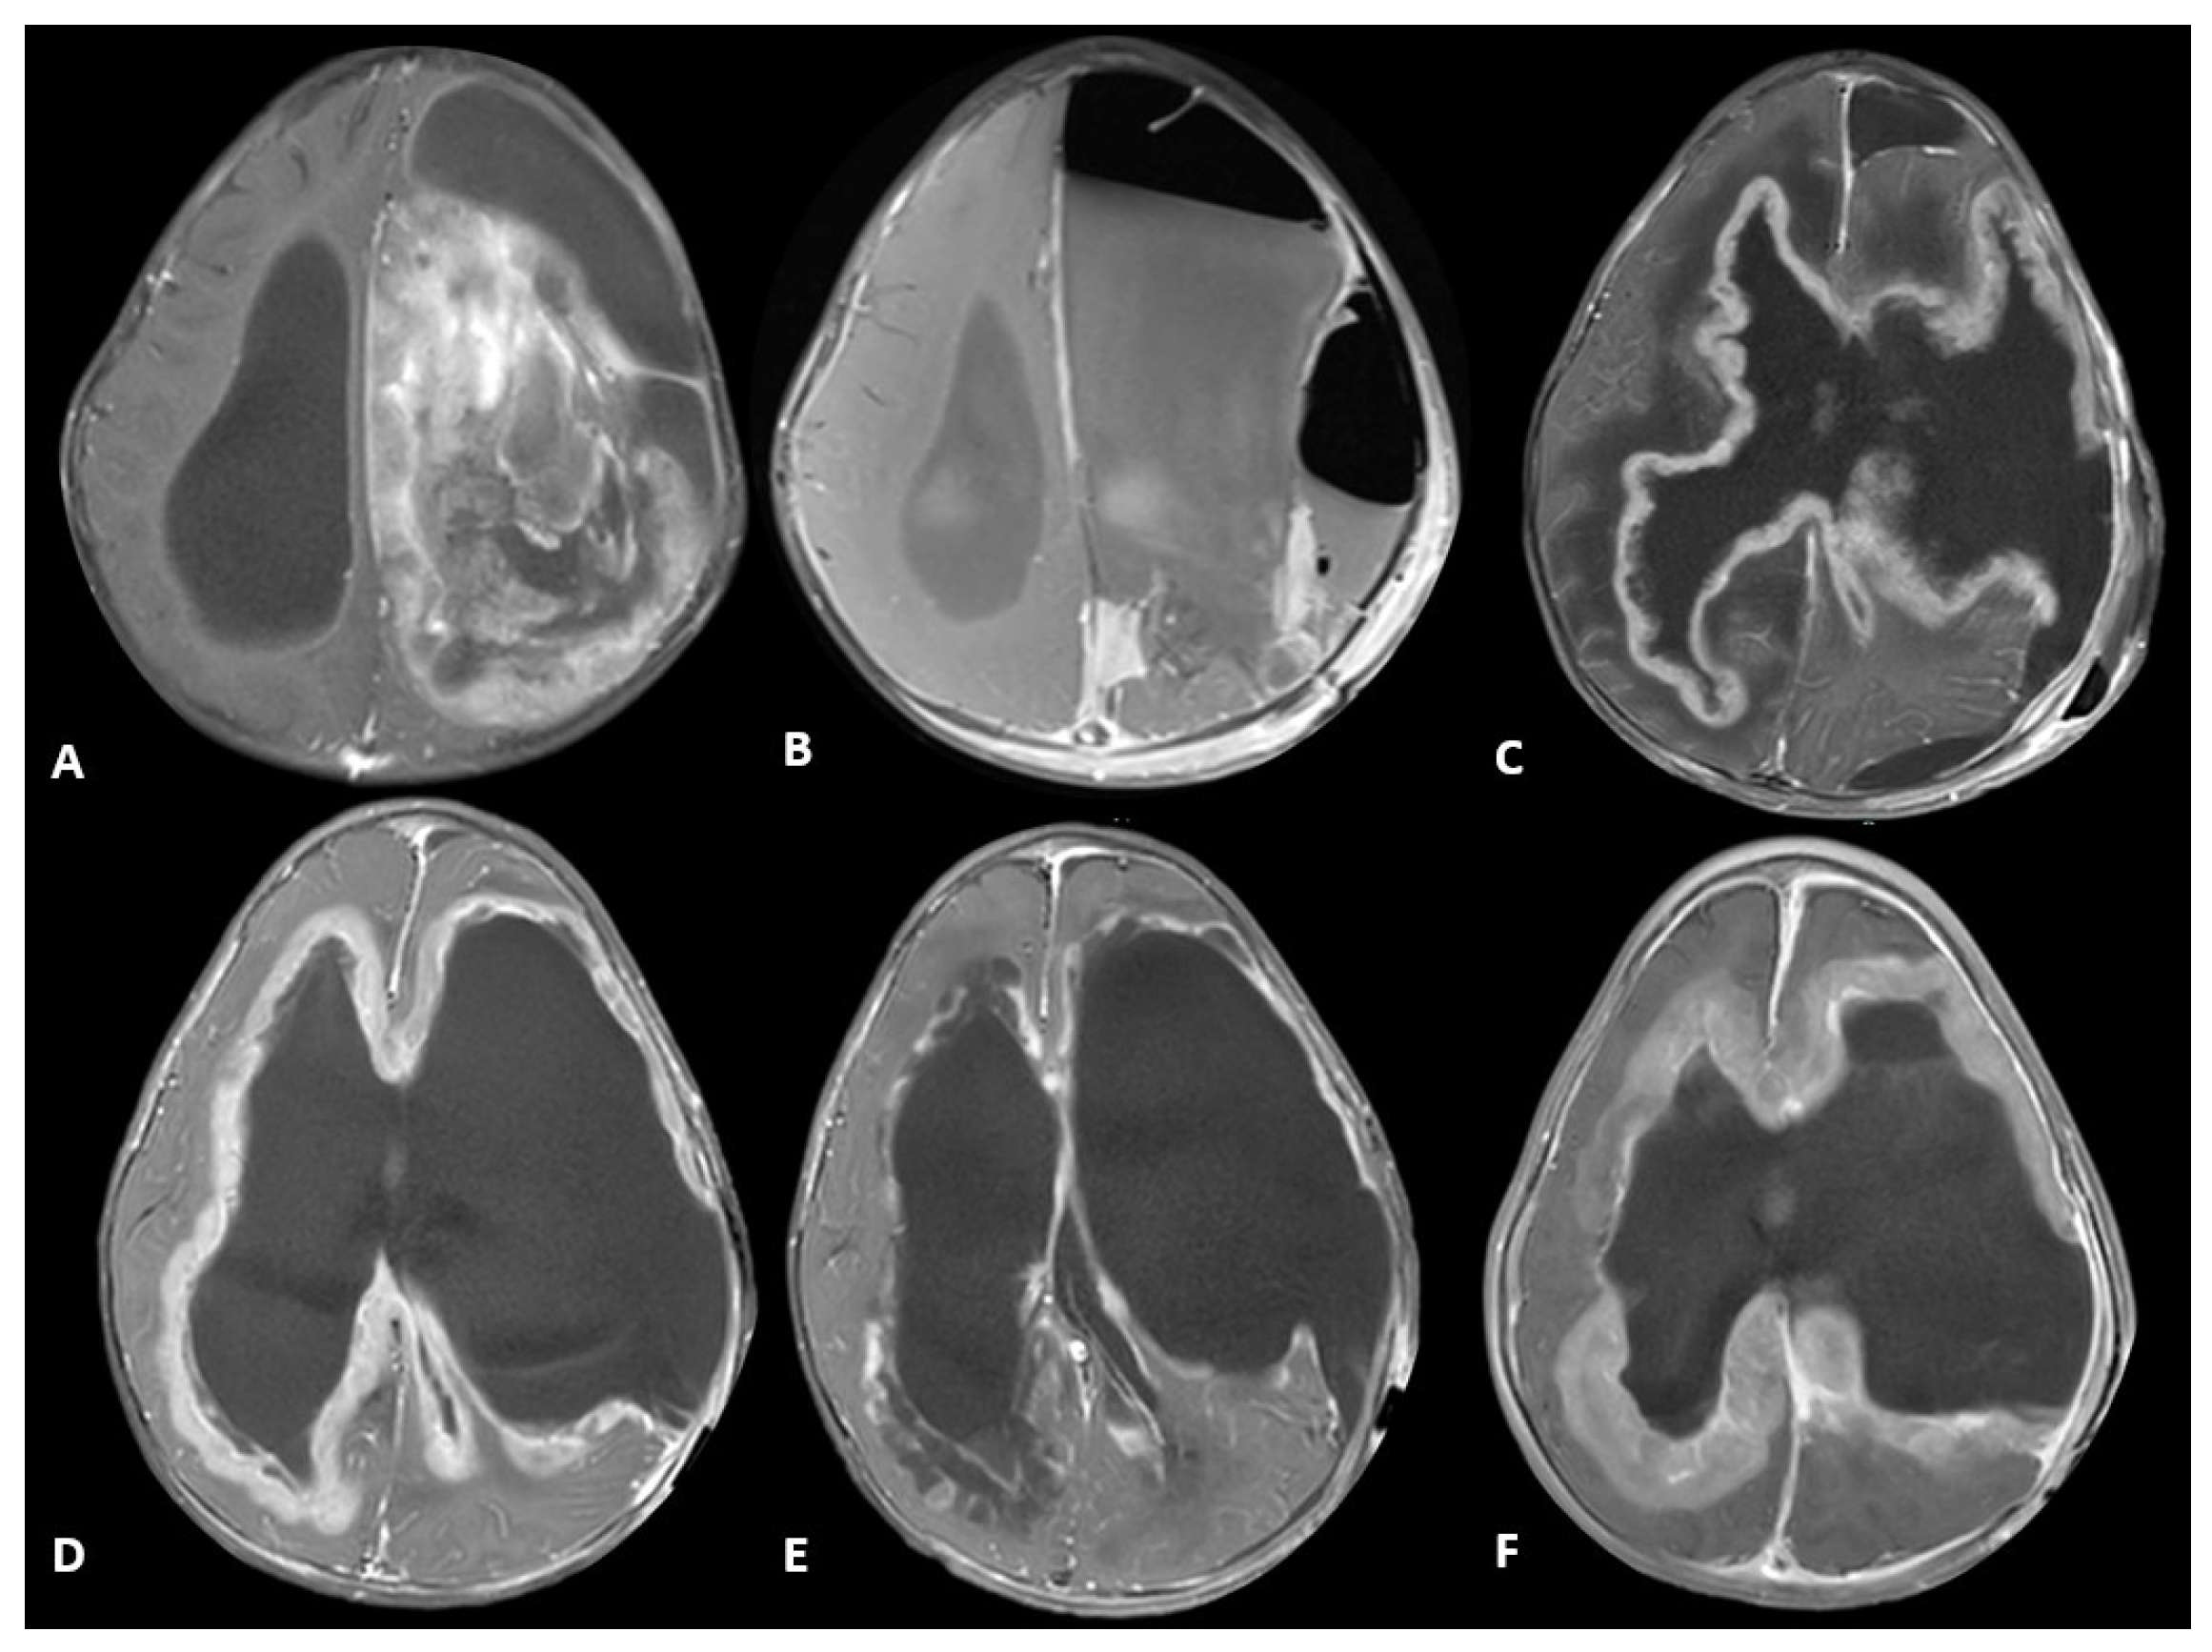

| Tumor Sample | Histopathology | Targeted Sequencing | Methylation Profiling Classification | Integrated Diagnosis | Treatment Regimen | |

|---|---|---|---|---|---|---|

| Patient 1 | Diagnostic | -Brisk mitotic activity -Gliosis in myxoid background -Vimentin positive -olig2 positive -S-100 positive | -CLIP2-MET fusion -CHEK2 frameshift alteration -CDKN2A, CDKN2B, MTAP loss | Infant-type Hemispheric Glioma | Infant-type Hemispheric Glioma, WHO-CNS Grade 4 | Systemic chemotherapy: Cyclophosphamide, Vincristine, Cisplatinum and Etoposide (2 cycles) Targeted agent: Cabozantinib |

| Patient 2 | Diagnostic | -Brisk mitotic activity -INI1 retained -P53 diffusely expressed -olig2 positive | -MBOAT2-ALK fusion -TP53 loss -MYCN copy gain | Diffuse Pediatric-type High-Grade Glioma, MYCN subtype | Diffuse Pediatric-type High-Grade Glioma, H3-wild-type and IDH-wild-type, CNS WHO Grade 4 | Radiotherapy with concurrent Temozolomide Targeted agent: Lorlatinib |

| Relapse | Similar to diagnostic sample, with olig2 loss | -MET copy gain -MBOAT2-ALK fusion -TP53 loss -MYCN copy gain | Diffuse Pediatric-type High-Grade Glioma, MYCN subtype | Diffuse Pediatric-type High-Grade Glioma, H3-wild-type and IDH-wild-type, CNS WHO Grade 4 | Target agents: Lorlatinib and Cabozantinib |